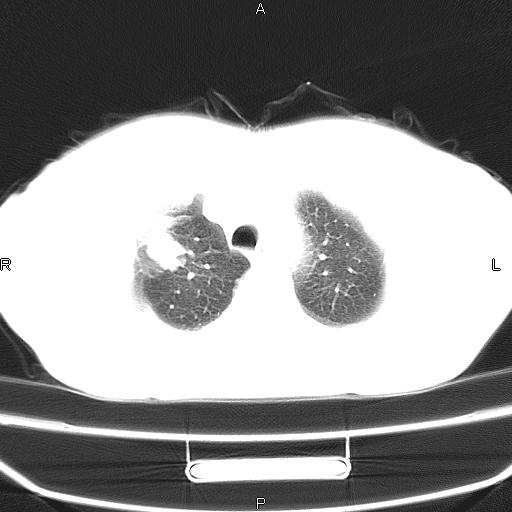

患者,女,66岁。健康体检胸部透视发现右上肺片状阴影。既往无不适,患者自诉三个月前曾有低热病史体温37.5左右一周。用药后缓解。至今无其它不适。请老师们指导指导。

考虑:右肺上叶周围型肺癌(分叶状肿块+砂粒状钙化+胸膜尾征)。

病灶见明显分叶、大小较大(大于3cm?),老年人,多考虑:肺癌,建议穿刺活检。

典型的中心型肺癌,尖段支气管阻塞。

右肺上叶周围型肺癌可能性大。

考虑:右肺上叶周围型肺癌